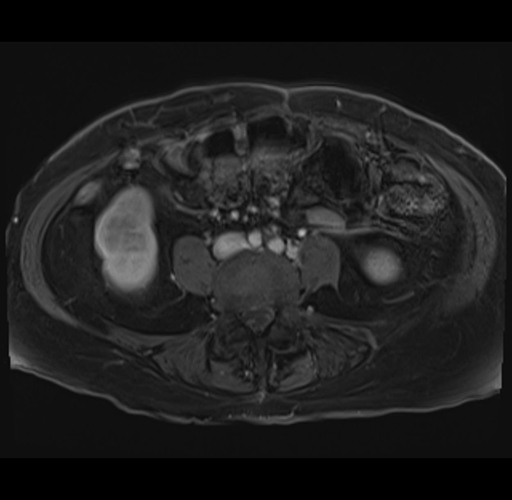

MRI T1